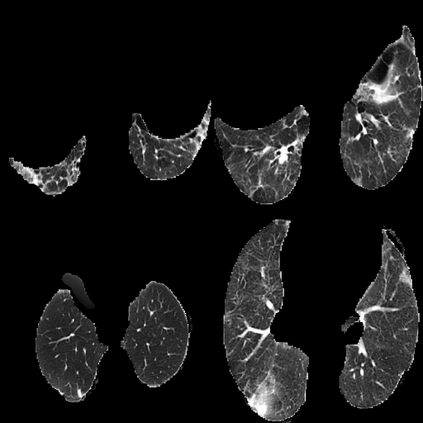

In the field of medical imaging, particularly in tasks related to early disease detection and prognosis, understanding the reasoning behind AI model predictions is imperative for assessing their reliability. Conventional explanation methods encounter challenges in identifying decisive features in medical image classifications, especially when discriminative features are subtle or not immediately evident. To address this limitation, we propose an agent model capable of generating counterfactual images that prompt different decisions when plugged into a black box model. By employing this agent model, we can uncover influential image patterns that impact the black model's final predictions. Through our methodology, we efficiently identify features that influence decisions of the deep black box. We validated our approach in the rigorous domain of medical prognosis tasks, showcasing its efficacy and potential to enhance the reliability of deep learning models in medical image classification compared to existing interpretation methods. The code will be publicly available at https://github.com/ayanglab/DiffExplainer.